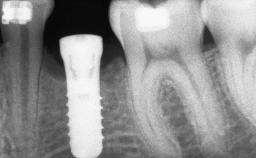

A 46-year-old woman was referred for treatment whose main complaints were mobility of her fixed partial dentures (right maxilla and left mandible) and periodontal bleeding during function. She also reported having taken systemic antibiotics to treat recurrent swelling in the area of the upper left molars. The patient had not seen a dentist for at least 2 years. She did not smoke and had no history of major systemic disease other than two minor orthopedic procedures some years back. The first-visit examination revealed poor plaque control, tooth mobility, periodontal disease, and a residual dentition widely associated with deep periodontal pockets.

| Bone Volume | Deficient vertically or deficient vertically AND horizontally |